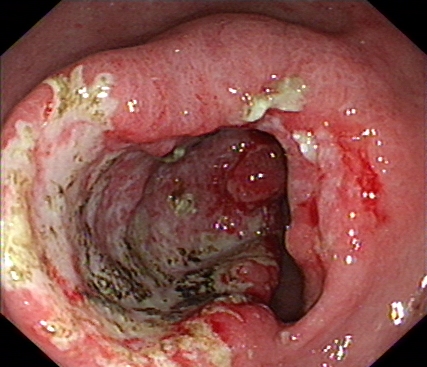

2020年1月,元旦刚过,大家都还沉浸在新年的喜悦中,来自隆安县的张阿姨一家却一筹莫展,张阿姨今年55岁,半年前开始出现上腹部胀痛不适,在当地医院一直按“慢性胃炎”服用中药及西药治疗,症状时好时坏。为了进一步治疗,来到我院就诊,内镜中心袁海锋主任亲自为其进行了无痛胃镜检查,经认真仔细观察发现胃内一处凹陷型病变,进一步行精细胃镜检查后,初步判断为早期胃癌病灶,而且病变侵犯深度局限在粘膜层内。经过与张阿姨及家属详细沟通后,决定用内镜下微创手术为其治疗。在内镜下确定病变边界后,顺利行内镜下粘膜剥离术(ESD)将病变完整切除。术后标本病理提示:早期胃癌(中分化管状腺癌)。治疗后一周,恢复良好,顺利出院,至今随访未诉明显不适。对于张阿姨一家来说,得了胃癌很不幸,但不幸中的万幸,她的胃癌被我们早期及时发现并完成了内镜下切除,避免进展为中晚期胃癌,使原本不富裕的家庭再雪上加霜。

图1 胃镜下早癌病灶

我们再来看一组胃镜图片,由胃溃疡到胃癌的过程(图片来源于网络)。患者未按医生医嘱,定期复查胃镜活检,最后进展为晚期胃癌。